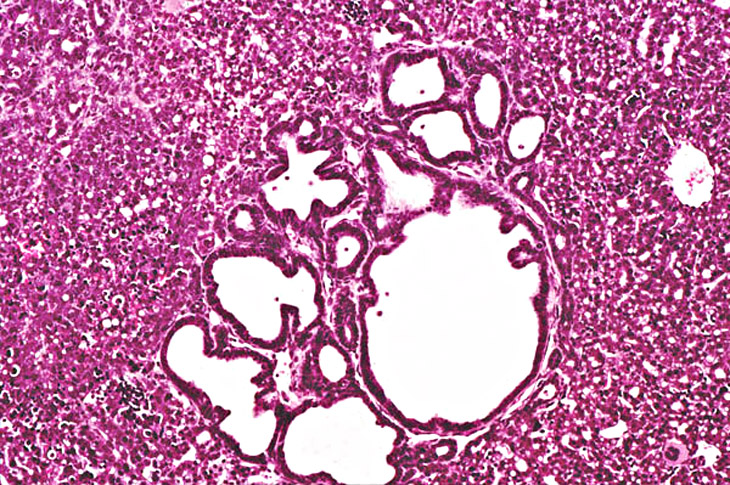

Focal areas of bile duct proliferation also arise within areas of ductular formation in 2-week old AL-TAg x AL-myc mice.

Increased severity of focal bile duct proliferation associated with an area of ductular formation in a 3-week old AL-TAg x AL-myc mouse.